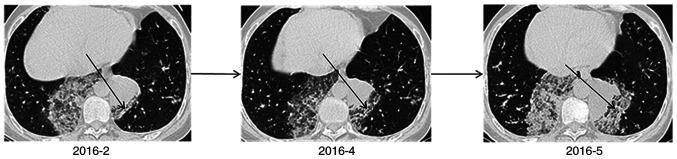

Patients with pneumonia-type lung cancer (PTLC) do not exhibit specific clinical features, which makes imaging diagnosis difficult. Therefore, the aetiology of the pathological changes occurring during PTLC remains unclear. The current study aimed to explore the possible mechanism of PTLC formation by CT scans and pathological analysis of the lungs. A retrospective analysis was conducted on the CT and pathological data of 17 cases of PTLC. The diagnosis of lung cancer was confirmed by pathology. The CT scans of nine patients indicated diffuse distribution of lesions in the lungs, whereas those of three patients indicated single-lung multi-leaf distribution, and those of the remaining five patients included single-leaf distribution. All patients demonstrated increased plaque or patchy density in the majority of the lesions located near the heart. The pathological types of the identified tumours were mucinous adenocarcinoma with adherent growth as the main sub-type. A large number of mucus lakes were observed, containing floating tumour cells, as determined by optical microscopy. In addition, a number of tumour cells were located in the residual alveolar wall of the observed mucus lakes. The results of the present study suggested that the mucinous adenocarcinoma tumour cells produced substantial quantities of mucus, and that the cells were scattered and planted along with the mucus through the airway, which led to possible development of pneumonia-type mucinous adenocarcinoma.